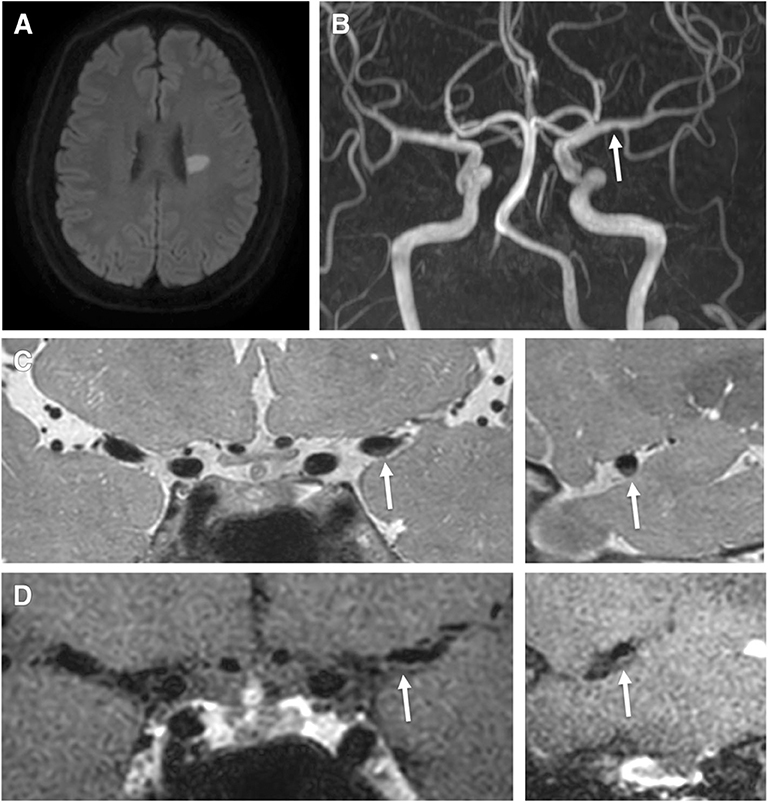

Plaque characteristics of coronary artery on CCTA. Multiplanar …

The plaque distribution on middle cerebral artery (MCA) walls. A …

(PDF) Vessel wall differences between middle cerebral artery and …

Frontiers | Factors for Enhancement of Intracranial Atherosclerosis in …

Coronary CT Angiography in Coronary Artery Disease: Correlation between …